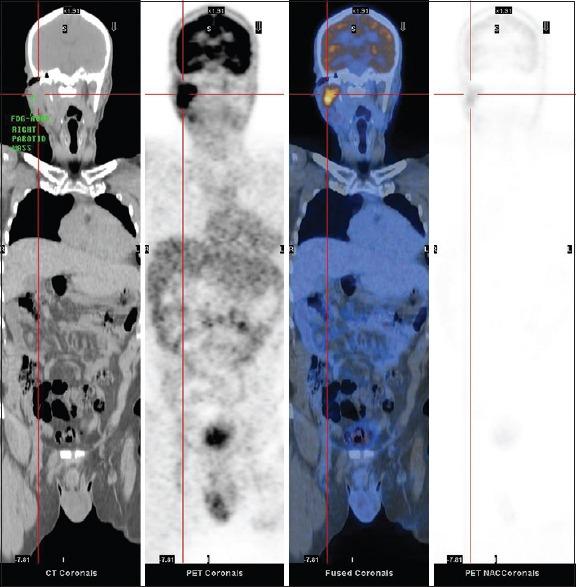

This case report explores the potential role of FDG PET/CT in HIV -associated systemic non-Hodgkin's lymphoma (HIV-NHLs). In our locality, there are a cumulative total of 5523 reported HIV infections cases since 1984. We reported a case of HIV-related Burkitt's lymphoma (BL) and a case of diffuse large B-cell lymphoma (DLBCL) that underwent PET/CT examination in our PET centre. In HIV-NHLs patients, we must be reminded that not all hypermetabolic foci represent lymphomatous lesions. There is a close correlation between the pattern of lymphoid tissue activation in FDG PET/CT and HIV progression in patients without HIV-related malignancy. The unique patterns of lymphoid tissue activation observed in HIV-infected patients have great clinical implications. Secondly, HIV-infected patients are prone to suffer from opportunistic infections due to immunosuppression, particularly in those with high levels of HIV viral loads. FDG PET/CT cannot reliably differentiate metabolic active lymphoma from other benign diseases such as inflammation in the context of low CD4 count and high viral loads. In those cases, benign markedly hypermetabolic foci can be erroneously interpreted as lymphoma, particularly in those normal-sized lymph nodes. Furthermore, FDG PET/CT may be useful for assessing the efficacy of HAART in suppressing HIV replication and detecting its complication such as lipodystrophy. FDG PET/CT may play a potential useful role in staging and management of HIV -associated systemic non-Hodgkin's lymphoma. Plasma variables such as viral loads and CD4 count must be taken into account during image interpretation. FDG PET/CT as a potential useful tool for diagnosis, treatment response assessment and disease relapse detection in HIV -associated systemic non-Hodgkin's lymphoma worth to be further explored.

本病例报告探讨了氟代脱氧葡萄糖正电子发射断层扫描/计算机断层扫描(FDG PET/CT)在人类免疫缺陷病毒相关系统性非霍奇金淋巴瘤(HIV-NHLs)中的潜在作用。自1984年以来,在我们当地累计报告了5523例HIV感染病例。我们报告了1例HIV相关的伯基特淋巴瘤(BL)和1例弥漫性大B细胞淋巴瘤(DLBCL),这2例患者均在我们的PET中心接受了PET/CT检查。对于HIV-NHLs患者,我们必须注意,并非所有高代谢灶均代表淋巴瘤性病变。在无HIV相关恶性肿瘤的患者中,FDG PET/CT中淋巴组织激活模式与HIV进展密切相关。在HIV感染患者中观察到的独特淋巴组织激活模式具有重要的临床意义。其次,由于免疫抑制,HIV感染患者容易发生机会性感染,尤其是那些HIV病毒载量高的患者。在CD4计数低和病毒载量高的情况下,FDG PET/CT无法可靠地区分代谢活跃的淋巴瘤与其他良性疾病,如炎症。在这些情况下,良性的明显高代谢灶可能会被错误地解释为淋巴瘤,尤其是在那些大小正常的淋巴结中。此外,FDG PET/CT可能有助于评估高效抗逆转录病毒治疗(HAART)在抑制HIV复制方面的疗效,并检测其并发症,如脂肪代谢障碍。FDG PET/CT在HIV相关系统性非霍奇金淋巴瘤的分期和管理中可能发挥潜在的有用作用。在图像解读过程中,必须考虑病毒载量和CD4计数等血浆变量。FDG PET/CT作为一种潜在的有用工具,在HIV相关系统性非霍奇金淋巴瘤的诊断、治疗反应评估和疾病复发检测方面值得进一步探索。